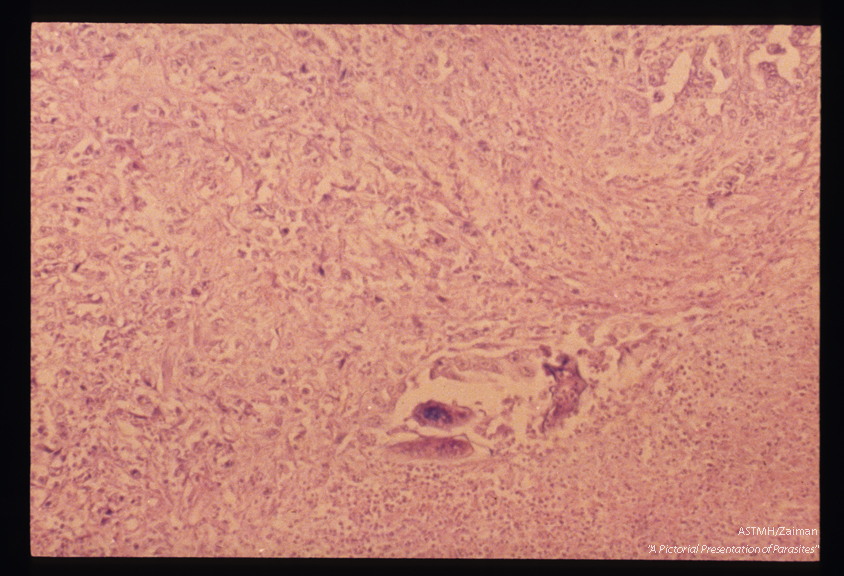

Eggs in an adenocarcinoma of the rectal mucosa. The ova are more deeply stained than the surrounding tumor.

Schistosoma mansoni

Description: Eggs in an adenocarcinoma of the rectal mucosa. The ova are more deeply stained than the surrounding tumor.